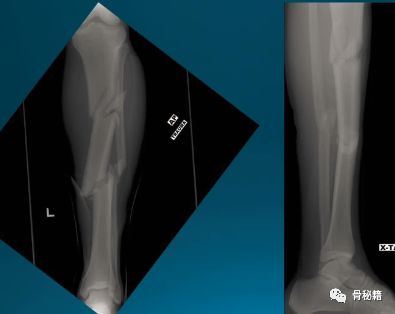

一个多阶段的胫骨骨折,看着移位不大

植入髓内钉后……